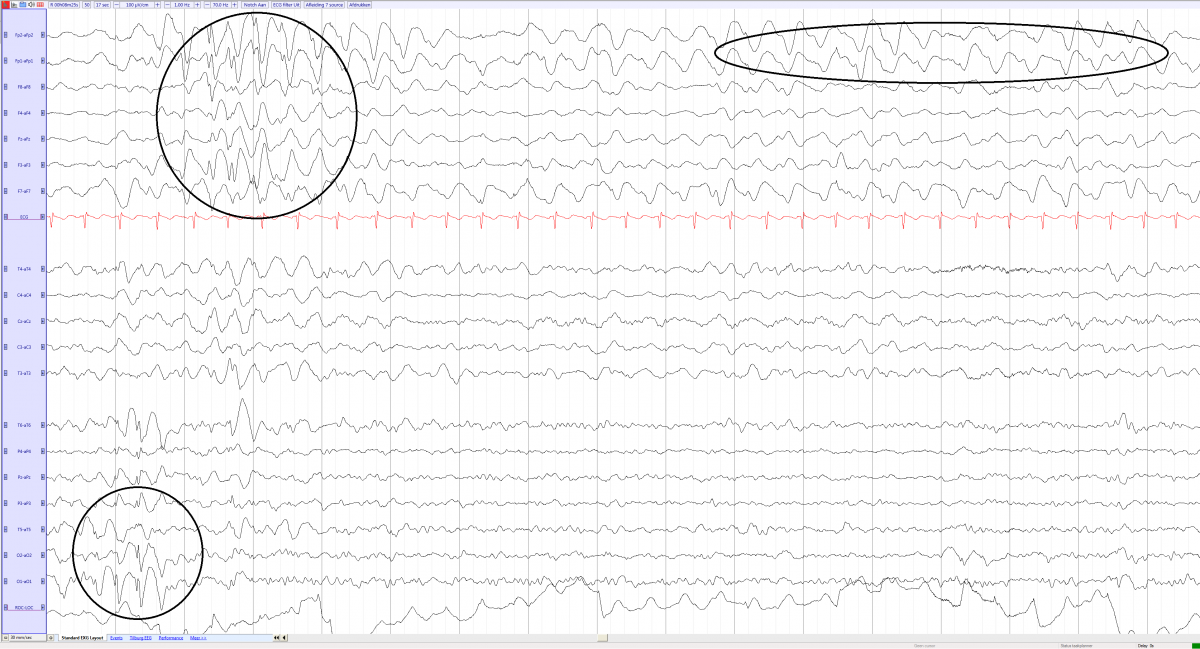

AS patients with a deletion of chromosome 15q have more prominent EEG abnormalities than patients with other genetic disturbances of the chromosome 15 region. Most of the authors agree about the existence of three main EEG patterns syndrrome AS which may appear in isolation or in various combinations in the same patient.

The pattern most frequently observed both in children and in adults has prolonged runs of high amplitude rhythmic Hz activity predominantly over the frontal regions with superimposed interictal epileptiform discharges.

The delta pattern was most specific for AS. Start Submission Become a Reviewer. BoydAngela HardenMichael Synerome.